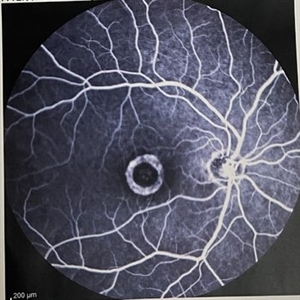

Doughnut-shape Atrophy After FTMH Surgery

Doughnut-shape Atrophy After FTMH Surgery

Feb 22 2023 by Tahmineh Motevasseli, MD

FA of a 70-year-old woman with a doughnut-shape atrophy secondary to FTMH surgery.

Photographer: Tahmineh Motevasseli, Shahid Beheshti Medical University, Labbafi Nejad eye clinic.

Imaging device: Heidelberg Spectralis, FA

Condition/keywords: atrophy